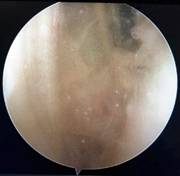

膝关节游离体 (关节镜清理术)

痛风性关节炎(关节镜清理术)

踝关节撞击综合征(关节镜清理术)